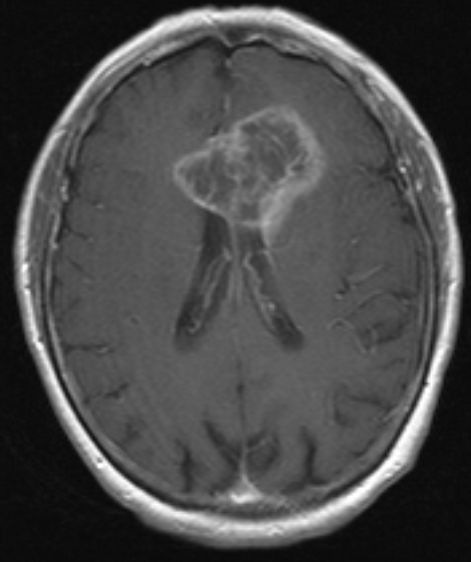

MRT: Schmetterlingsgliom |

![]() |

![]() | ||